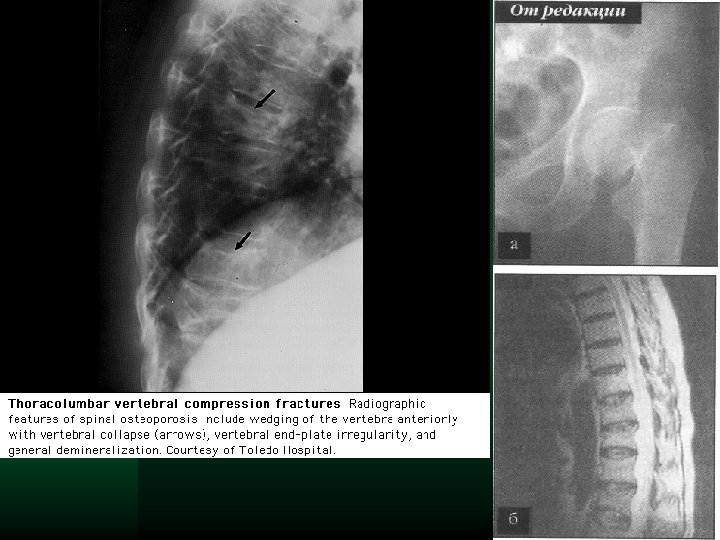

Компрессионный перелом Th 9, Th 11 у пациентки с тяжелым стероидозависимым остеопорозом

До лечения

Рентгенография Чувствительна только при потере 25 – 30 % кости